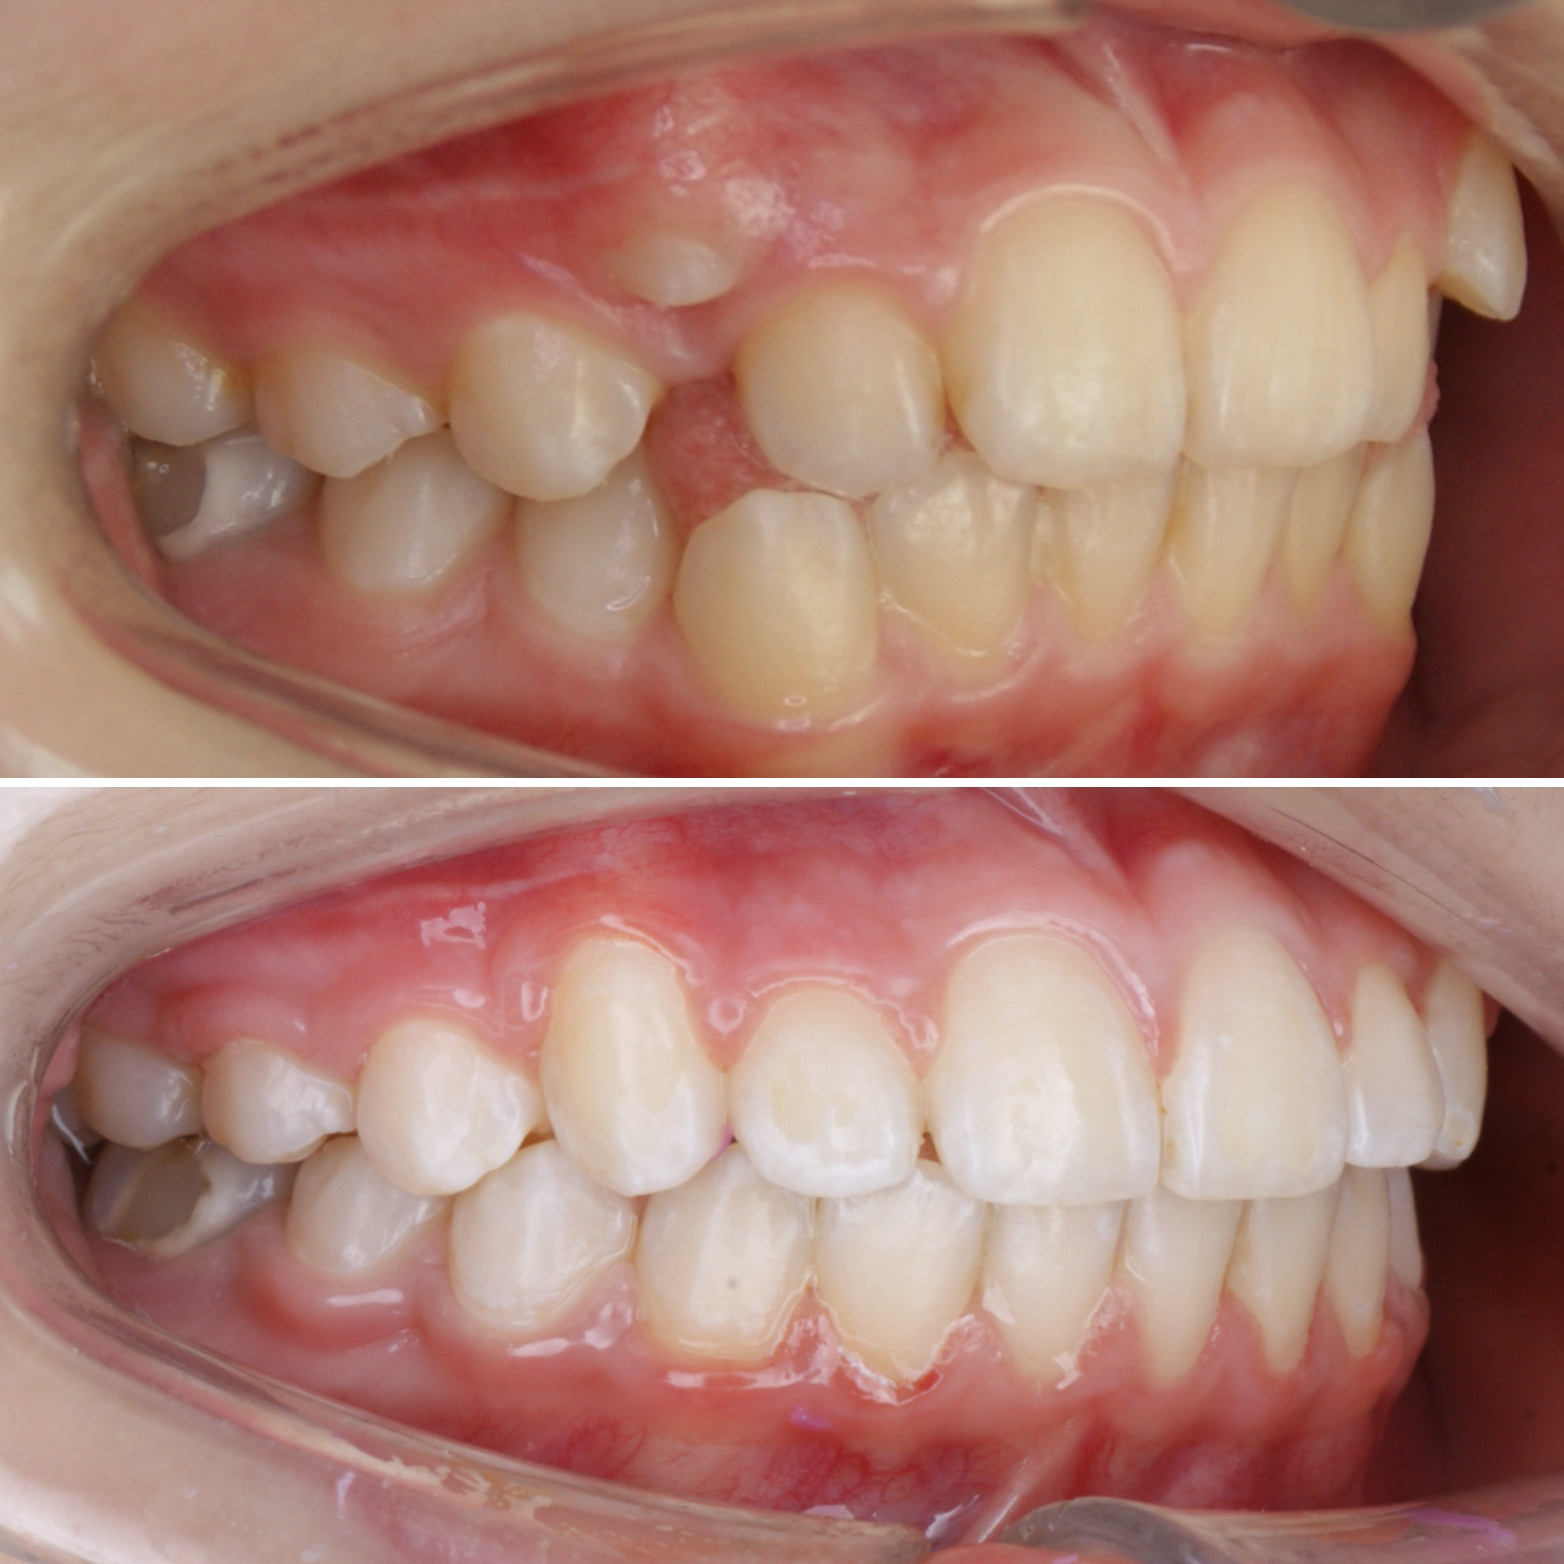

✔Глубокий прикус, дистальный прикус с пространством (щелью) между верхними и нижними резцами, скученное положение зубов, заблокированное нёбное положение верхнего левого зуба ✔Лечение на металлической самолигирующей системе Damon

✔Пациент, 12,5 лет на момент старта ✔Общий срок лечения 18 месяцев ✔Брекеты Damon Q ✔Дистальный, перекрестный, глубокий прикус, смещение нижней челюсти, несоответствие средних линий и сужение зубных рядов, скученность зубов, недостаток места для верхних клыков